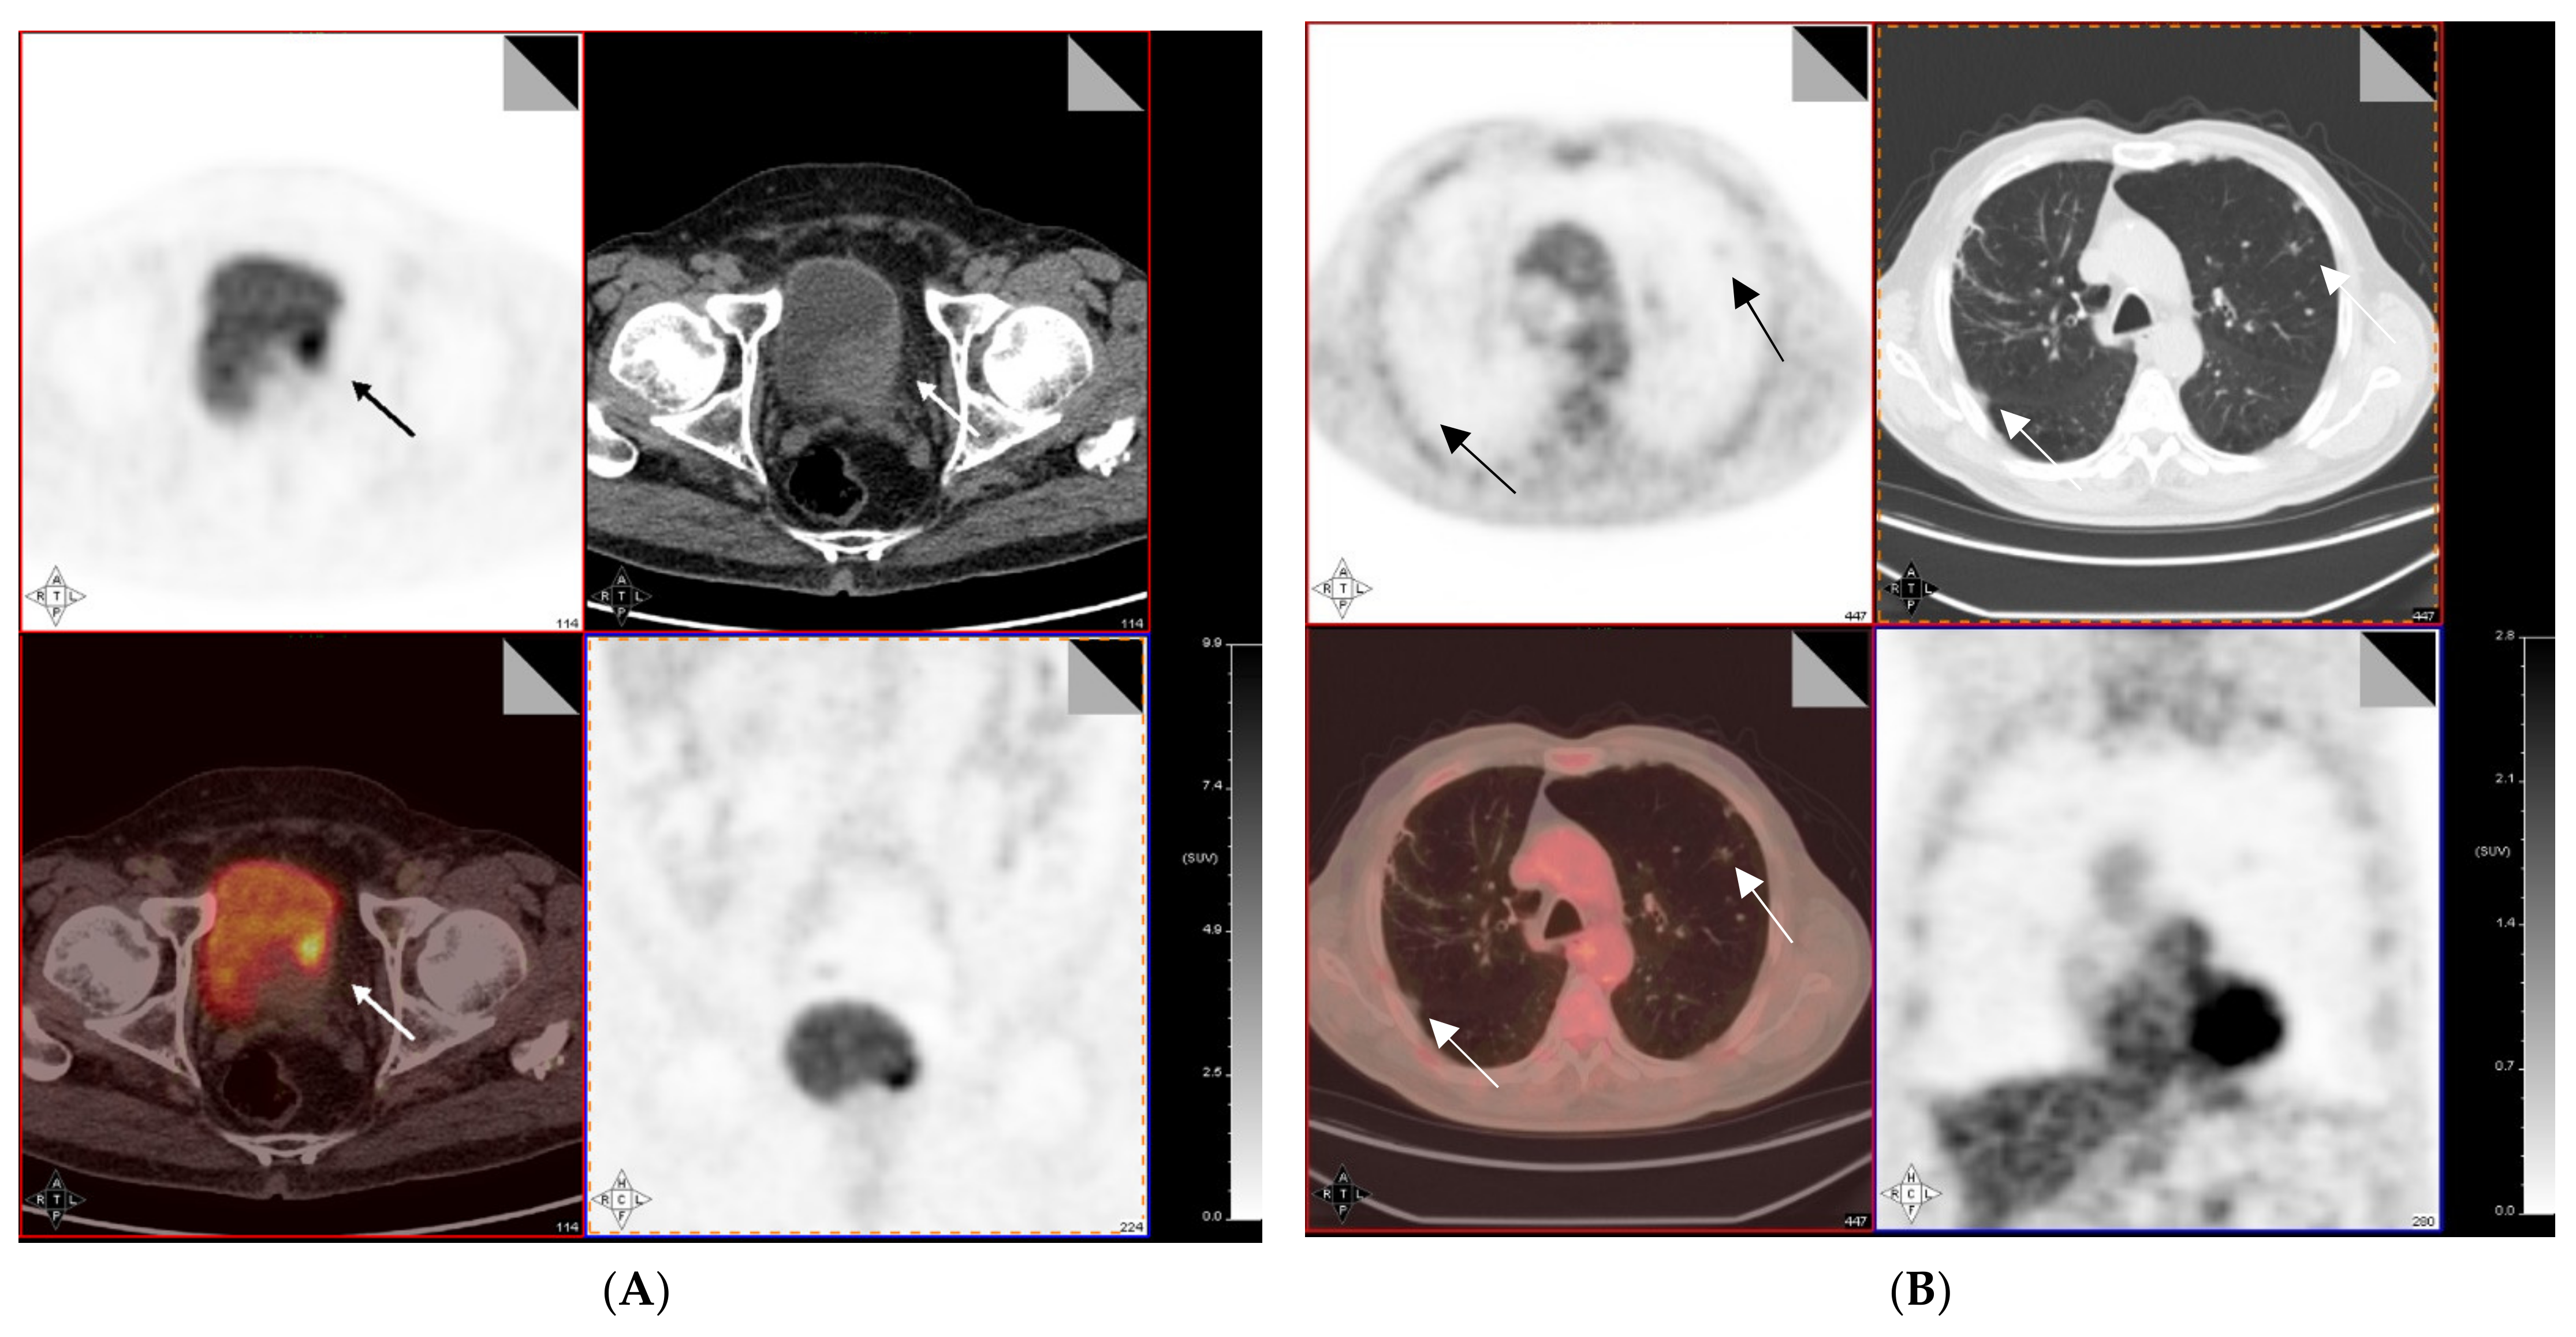

4. 18F-FDG PET/CT for Preoperative Lymph Node Staging of MIBC

5. 18F-FDG PET/CT for Restaging and Response Evaluation of MIBC Following Neoadjuvant Chemotherapy